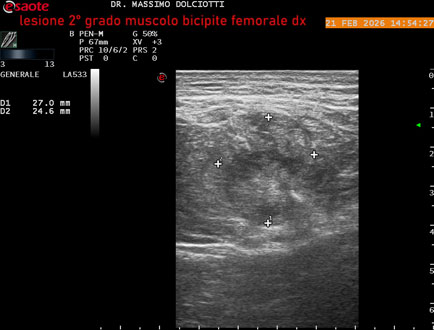

Ecografia del: 21/02/2026

Strumento: Esaote MyLab Eight

Sonda: Lineare Multifrequenza 3-13 MHz

Età Paziente: M 49 anni

Motivazione dell'esame: da 10 giorni dolore insorto durante la corsa.

Commento all'esame: le immagini ed il video documentano, al muscolo bicipite femorale destro, in sede prossimale, area disomogenea, ipoecogena, delle dimensioni di 27 x 24 mm (misura ottenuta per asse corto o trasversale) e delle dimensioni di 51 x 33 mm (misura ottenuta per asse lungo o longitudinale), da ricondurre a lesione muscolare di 2° grado con modica raccolta sieroematica intramuscolare.

Conclusioni: lesione di 2° grado al muscolo bicipite femorale destro (grade 2 injury to the right biceps femoris muscle).